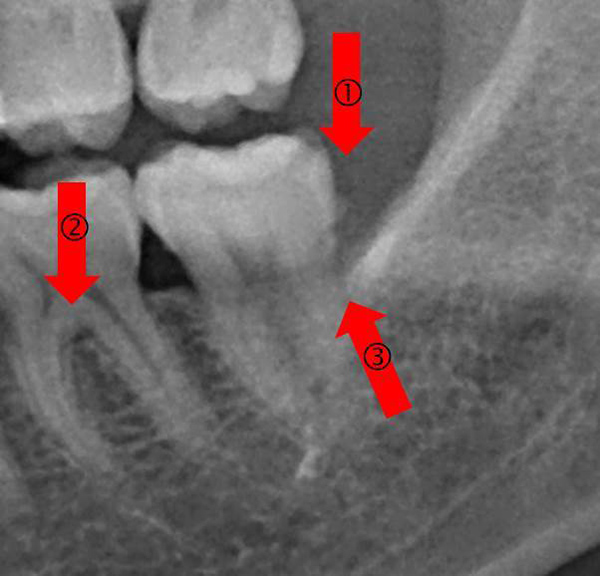

| 治療前(紅色箭頭) : 1.牙齒表面粗糙,可見牙齦下大塊牙結石 2.牙根分岔區可見明顯骨流失黑影 3.牙齒周圍骨質疏鬆 ![]() |